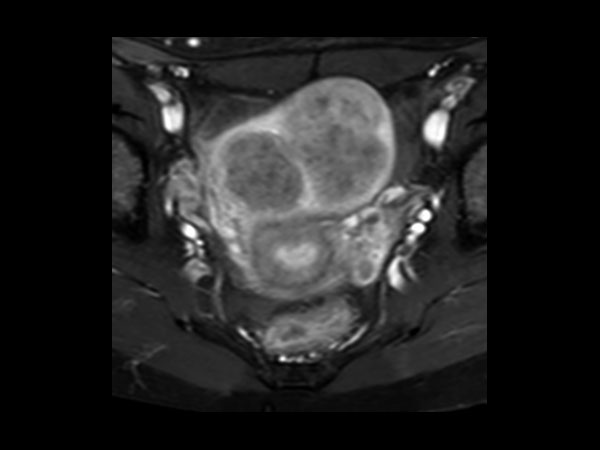

Female Pelvis

Toyonaka Hospital, Japan